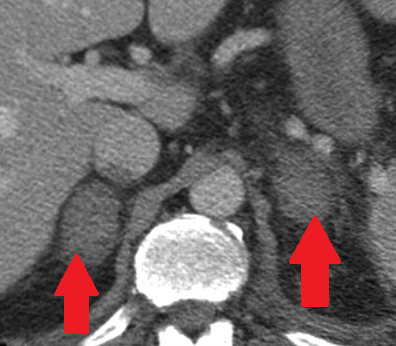

Αριστερό περινεφρικό αιμάτωμα και δεξιό αιμάτωμα λαγονοψοΐτη — αντιπηκτική αγωγή (Ευγενική παραχώρηση Dr. V. Penopoulos)